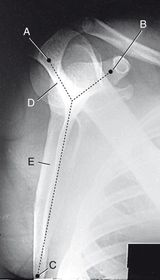

A. greater tubercle (tuberosity) B. intertubercular groove (bicipital) C. surgical neck D. head E. anatomic neck F. lesser tubercle (tuberosity) G. deltoid tuberosity H. humeral body (shaft)